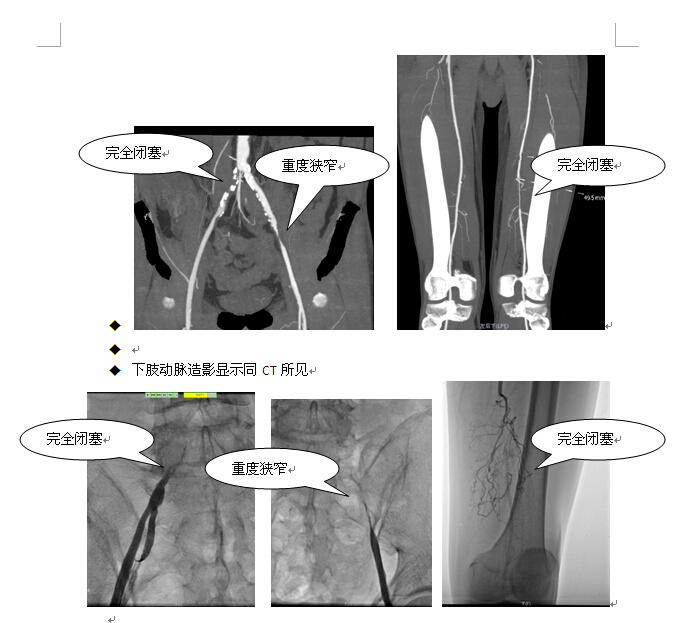

u  我院下肢动脉CT显示右侧髂总动脉近段闭塞。左侧髂外动脉近中段次全闭塞。左侧股动脉中远段闭塞。左侧胫前动脉远段及足背动脉闭塞。